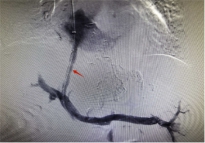

随着手术方案的敲定,张爷爷随之转入介入血管外科,团队完成充分术前评估与准备工作后,在杨维竹教授的带领指导下,介入外科团队依托精准影像导航技术,通过患者颈部微小穿刺点,将导管精准送达目标血管。团队以精细操作完成肝内分流通道的构建,同时对出血责任血管进行致密栓塞,整个手术耗时不足1小时,过程顺利。术后患者门静脉压力显著下降,止血、减压效果立竿见影。